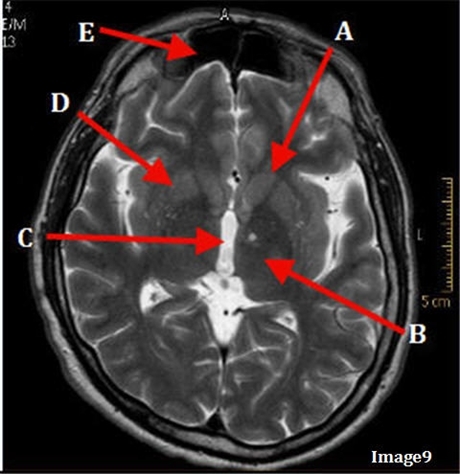

Image weighting and axis

T2 Axial

A

Caudate Nucleus

B

Thalamus

C

Third ventricle

D

Lentiform Nucleus

E

Frontal Sinus